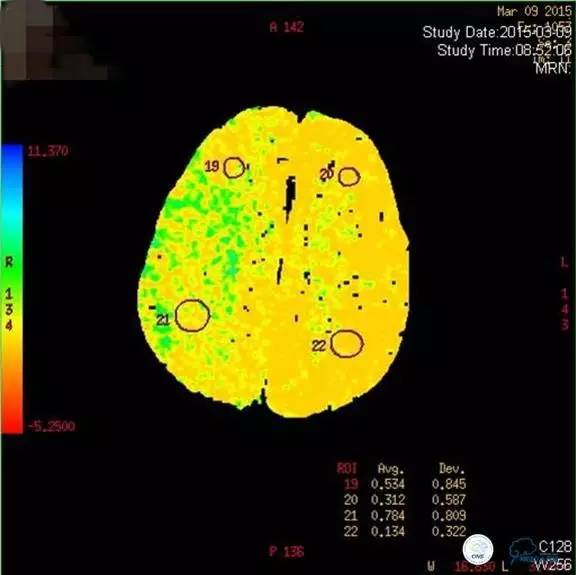

患者:49岁男性,左侧偏瘫1个月,药物治疗、康复训练效果不好,转我院,肌力0~1级。

core-clilnical明显不匹配,是介入开通的合适患者。